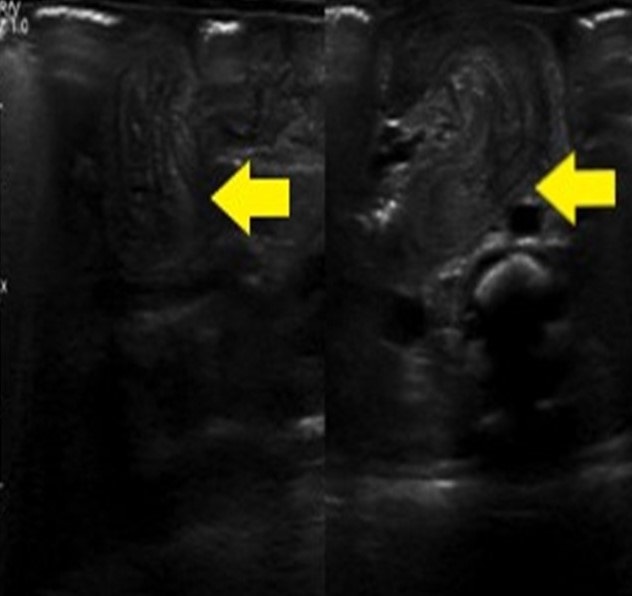

Figure 2

Intussusception 35 cm distal to the Angle of Treitz.

She underwent laparotomy that revealed a 10 cm long edematous, erythematous intussusceptum segment in the jejunum, 35 cm distal to the angle of Treitz (Fig. 2). It was reduced manually without any signs of perforation. The baby was kept nil per os in NICU for 2 days and was started oral feeds from postoperative day 3 after resolution of gastric aspirate. The baby was discharged and is gaining weight at 2 months of follow-up.